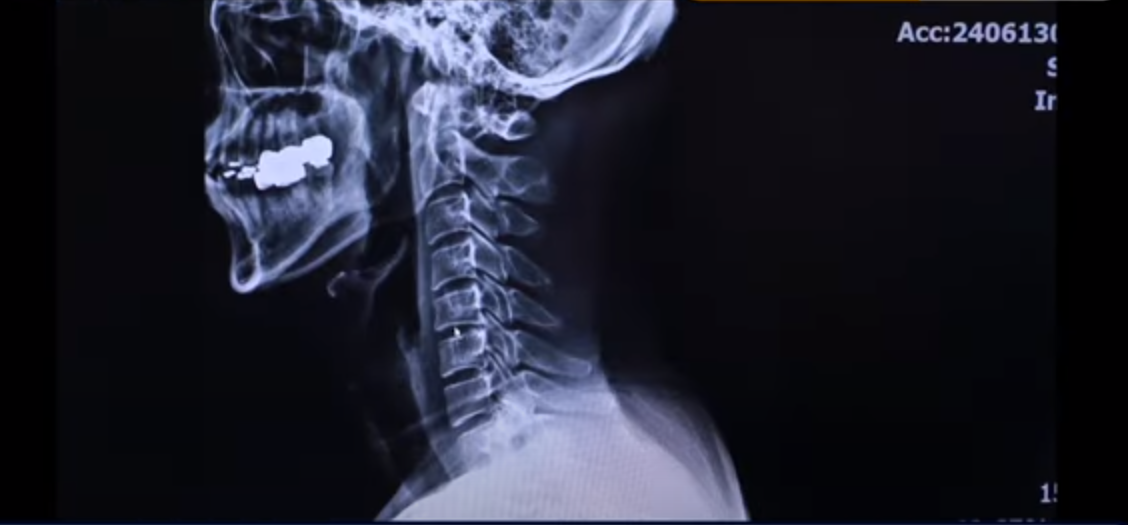

저희가 왜 목 디스크 치료가 쉽다고 하냐면 엑스레이 사진을 보면서 설명 드리도록 하겠습니다. 이분 엑스레이 사진입니다. 보시다시피 완전히 일자입니다. 이런 걸 일자목이라고 합니다.

그리고 이게 일자면서도 앞으로 밀려나가 있습니다. 그래서 이걸 거북목이라고 합니다. 이런 형태의 목을 가지신 분들은 이 목 주변 근육이 정상일 수가 없습니다. 엄청나게 뭉쳐 있고 굳어 있고 특히 이 앞쪽 근육들은 머리가 앞으로 밀려나가다 보니까 짧아져 있습니다. 짧아져 있기 때문에 머리를 자꾸 앞으로 잡아당기는 겁니다. 그래서 거북목 환자들이 좋은 자세를 유지하고 싶어도 유지하기가 어려운 이유가 바로 이쪽 근육들이 심하게 단축돼 있고 뭉쳐 있기 때문입니다.

이렇게 근육들이 뭉쳐 있으면 이 뼈들을 자꾸 잡아당기기 때문에 이 중간에 있는 신경 구멍을 더 좁히는 효과를 가져옵니다. 그래서 자꾸 잡아당기기 때문에 신경학적 증상이 더 심해질 수밖에 없는 겁니다. 그래서 목 디스크 치료가 쉽다고 하는 이유는 저희는 목 근육 재활 치료를 하지 않습니까?